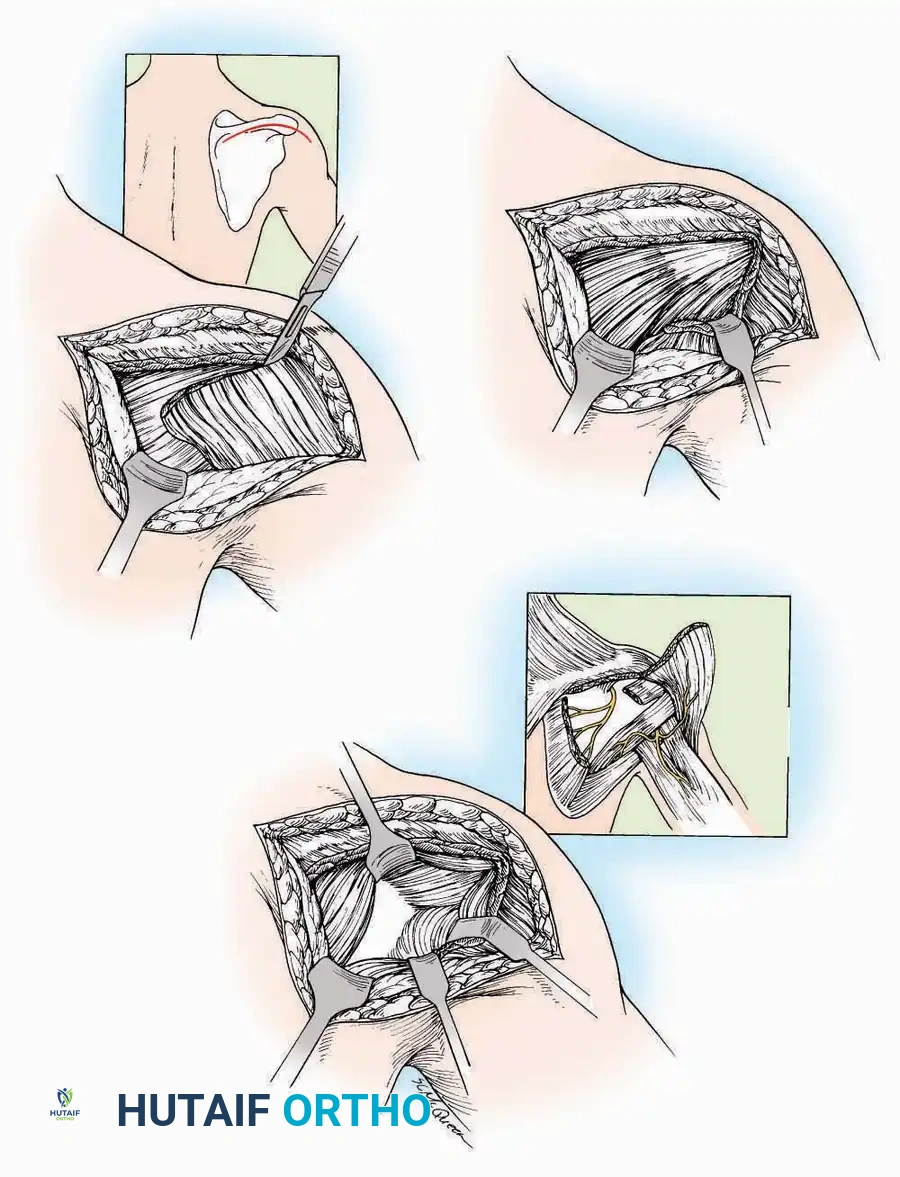

Anterolateral Approach

The anterolateral approach is widely considered the "universal incision" for the foot and ankle. It provides unparalleled access to the ankle joint, the talus, and the majority of the tarsal articulations, while safely avoiding the major anterior neurovascular bundle. The only tarsal joints inaccessible via this route are the naviculocuneiform joints (specifically the medial and intermediate).

Indications: Total talectomy, triple arthrodesis, ankle arthrodesis, and open reduction of complex talar neck fractures.

Surgical Technique:

* Incision: Begin over the anterolateral aspect of the leg, medial to the fibula and 5 cm proximal to the ankle joint line. Carry it distally over the joint, crossing the anterolateral aspect of the talar body and the calcaneocuboid joint, terminating at the base of the fourth metatarsal.

* Superficial Dissection: Incise the superficial fascia and the superior and inferior extensor retinacula down to the periosteum of the tibia and the ankle joint capsule.

* Vascular Ligation: This trajectory usually requires the identification and ligation of the anterolateral malleolar and lateral tarsal arteries.

* Nerve Protection: Retract the skin edges carefully. Identify and protect the intermediate dorsal cutaneous branches of the superficial peroneal nerve (SPN), which frequently cross the distal aspect of this incision.

* Muscle Management: Identify the origin of the extensor digitorum brevis (EDB) muscle on the lateral calcaneus. Divide it in the direction of its fibers, or detach its origin entirely and reflect it distally to expose the subtalar and calcaneocuboid joints.

* Deep Exposure: Retract the extensor digitorum longus (EDL) tendons, the dorsalis pedis artery, and the deep peroneal nerve (DPN) medially. Incise the anterior ankle capsule to expose the tibiotalar joint.

* Tarsal Exposure: Expose the talonavicular joint by dissecting deep to the extensor tendons and incising its capsule transversely. Continue laterally through the capsule of the calcaneocuboid joint. By excising the fat pad within the sinus tarsi (lateral and inferior to the talar neck), the posterior facet of the subtalar joint is brought into direct view.